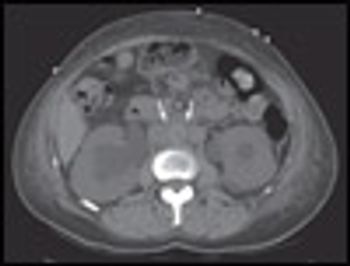

A 69-year-old man with stage II chronic kidney disease due to hypertension fell from his bicycle and presented to the emergency department (ED) with abrasions, ecchymoses, and a 3-cm laceration on his right leg. The patient was an avid cyclist. His wounds were cleaned and the laceration sutured. There were no fractures, and the patient was discharged home.